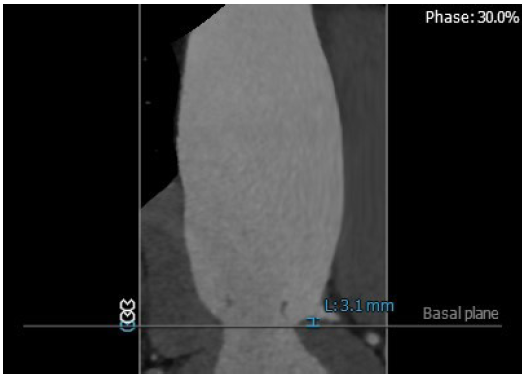

3. 患者左侧冠脉开口高度低LCA:3.1mm,左冠瓣瓣叶长度约12.4mm;右侧冠脉开口高度可RCA:16.8mm;

左冠高度:3.1mm